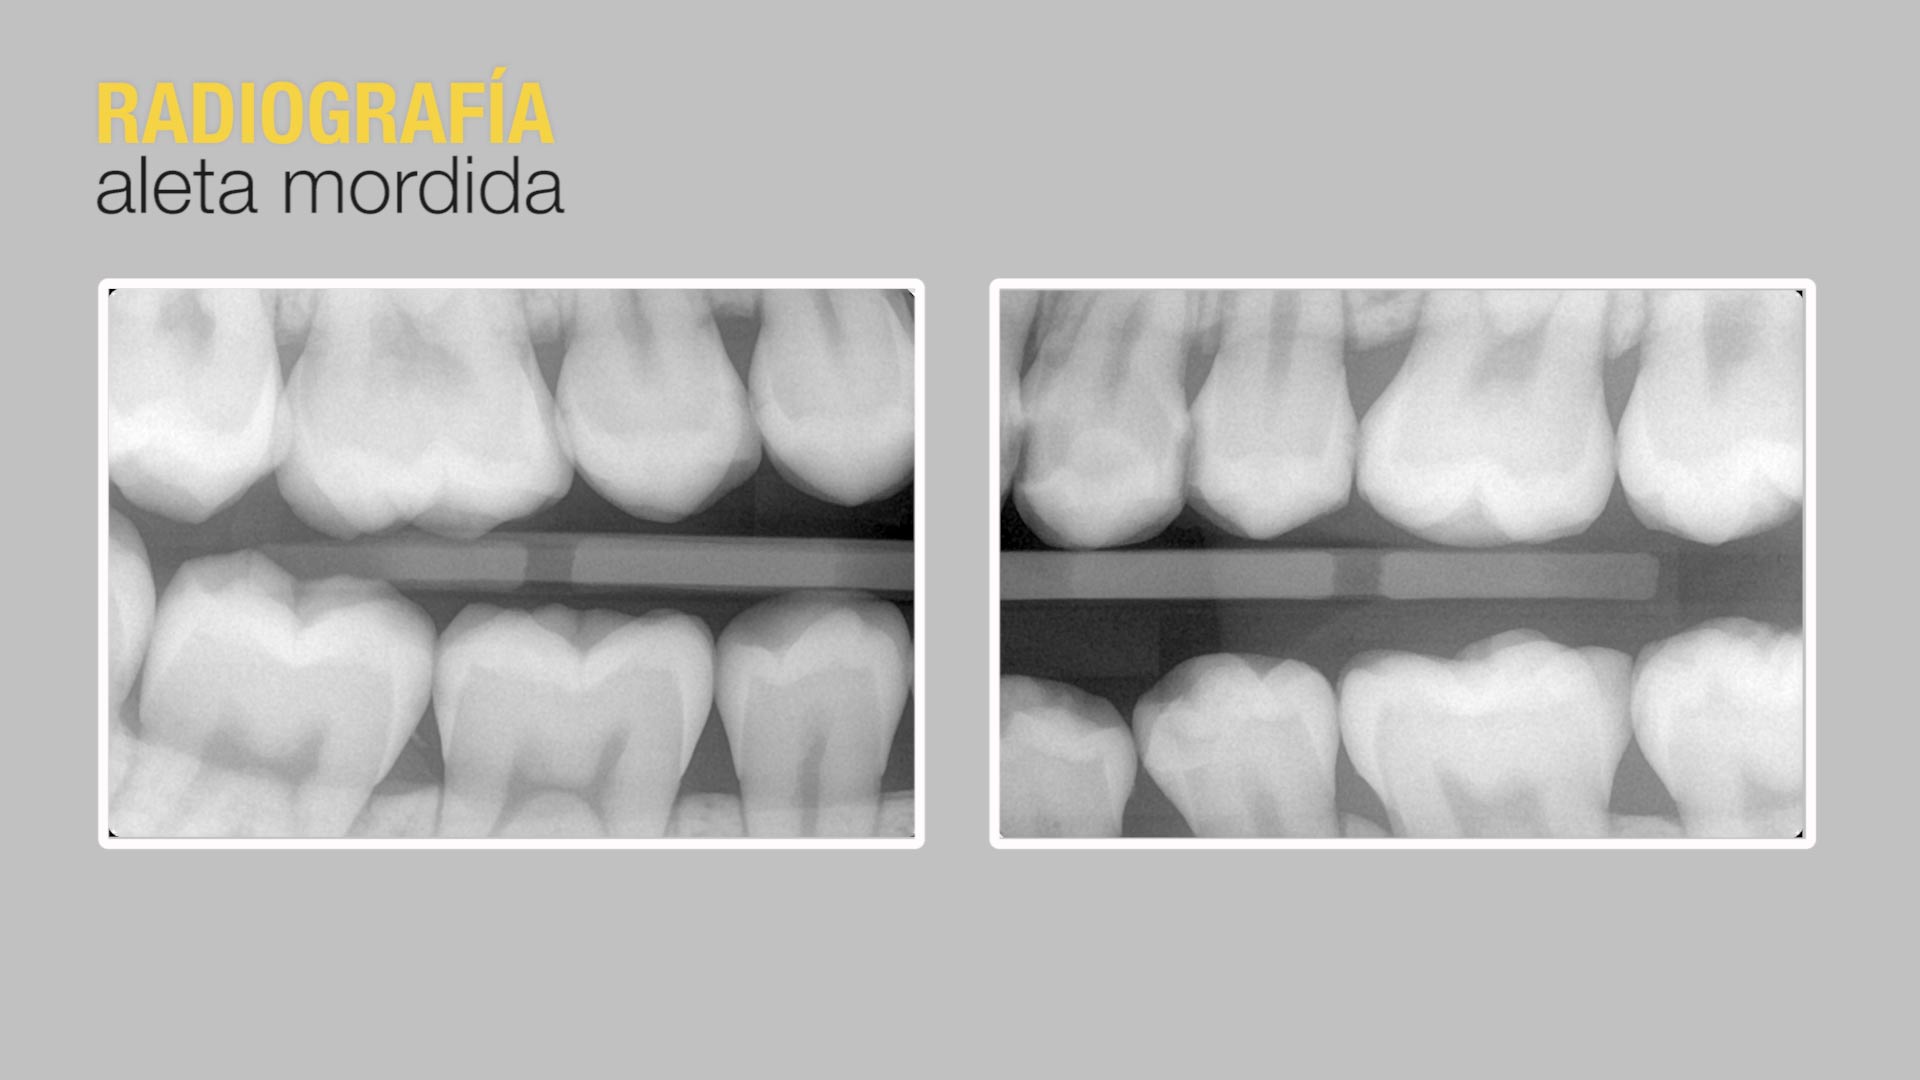

Radiografía aleta de mordidaLo primero que se realiza es una radiografía de aleta de mordida, o lo que es lo mismo, una radiografía interproximal. De este modo, se pueden apreciar caries muy pequeñas, que no se pueden diagnosticar de manera clínica.